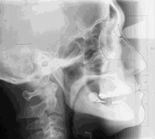

古い入れ歯を装着 した時のX線写真

古い入れ歯では 下あごは前に出ています (黒線)